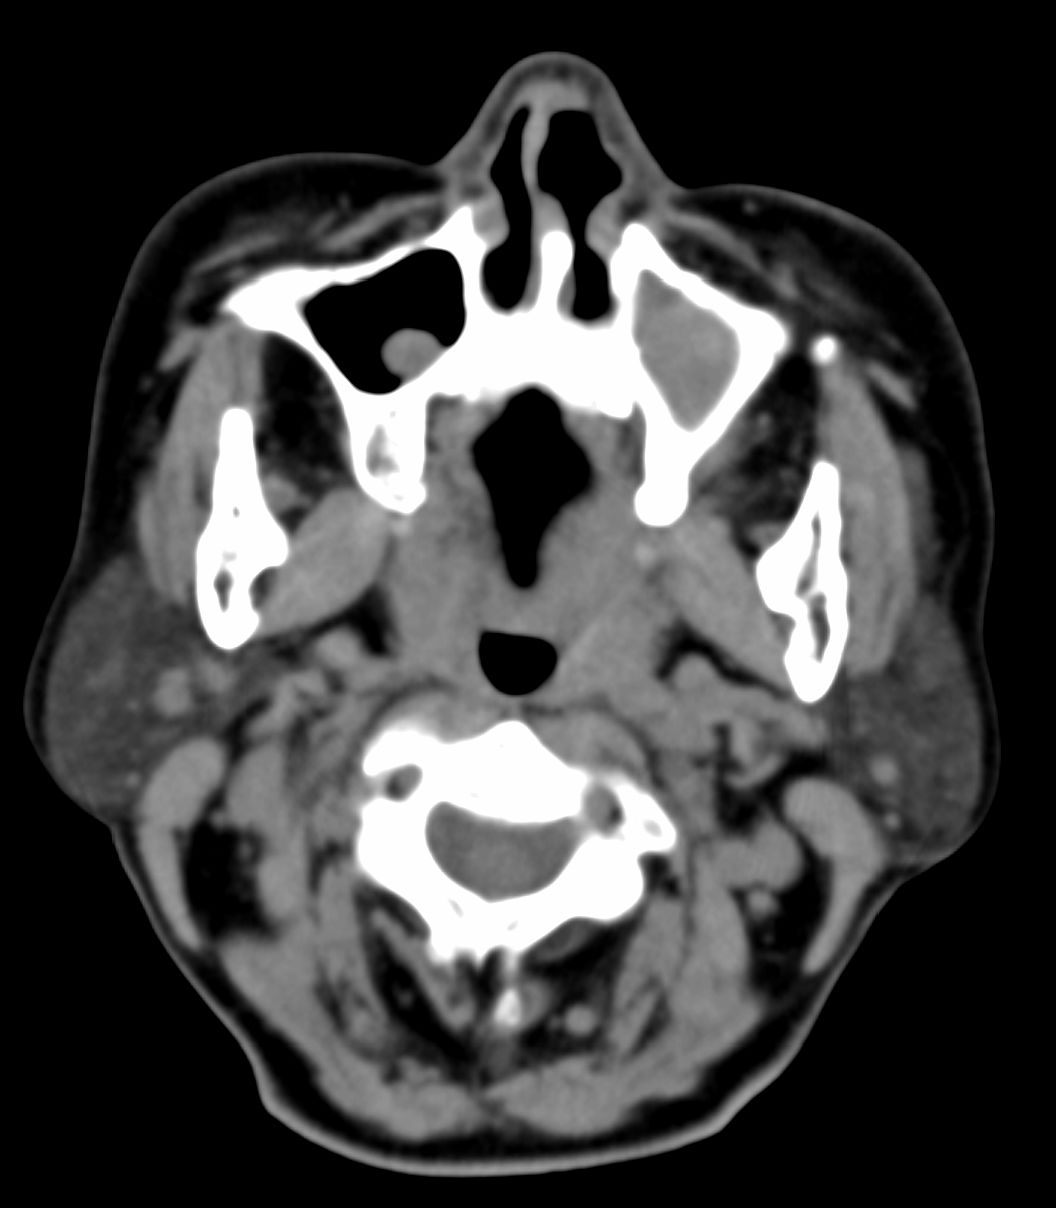

女,69岁。鼻出血2月多。(会诊病史就这样简单)鼻副窦ct检查如下:

左侧鼻腔及上颌窦见软组织块影,左侧上颌窦腔扩大,骨质吸收,右侧上颌窦见半圆形软组织密度影,鼻中隔向右侧弯曲,左侧鼻和鼻窦内翻型乳头状瘤可能性大,建议增强。

左侧上颌窦及鼻腔内见软组织密度影,其内密度不均匀,见斑片状高密度影,右侧上颌窦腔明显扩大,窦壁吸收变薄,鼻中隔右偏,右侧上颌窦见一半圆形软组织密度影,边界清楚,其内密度均匀。诊断,1、左侧鼻腔及上颌窦内翻乳头状瘤可能性大,上颌窦癌,息肉及霉菌性上颌窦炎待除外。2、右侧上颌窦粘膜下囊肿。

1)考虑左侧上颌窦内翻乳突状瘤突入左侧鼻腔。2)副鼻窦炎,右侧上颌窦黏膜下囊肿。

病理:霉菌性左侧上颌窦炎伴左侧上颌窦纤维组织增生。

窦腔密度不均匀增高,无明显钙化征象,后外侧及内侧窦壁膨胀明显,局部破坏消失,筛窦受累及,但双侧对比发现左侧窦壁骨质有硬化增白现象,这可能是支持左侧霉菌性上颌窦炎的主要依据点。